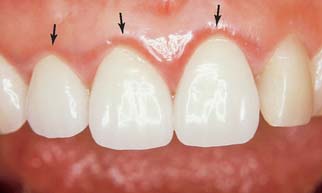

Fig. 32-4 Postcementation monitoring of plaque control is necessary around recently cemented restorations. Poor oral hygiene has led to gingival inflammation (arrows).